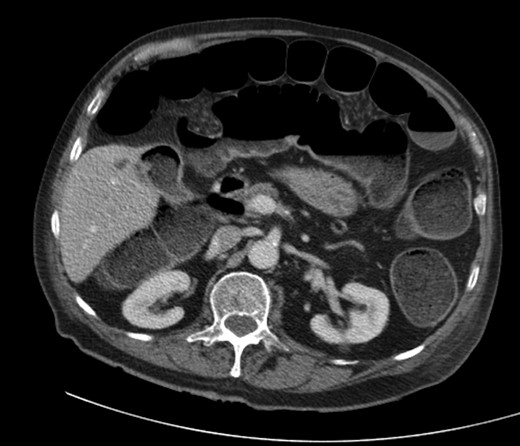

A 92-year male, with no significant co-morbidities apart from peptic ulcers, was admitted with 6 days of obstination. On examination he was dehydrated, with a hugely distended abdomen but no signs of peritonitis. Blood showed features of dehydration and plain abdominal X-ray demonstrated both small and large bowel dilatation, but no obvious causal pathology. A contrast-enhanced computed tomography scan revealed a 2.5-cm partially calcified gallstone impacted at the descending colon-sigmoid junction (Fig. 1). There was no stricture or diverticular disease distal to the stone. A cholecysto-colic fistula could be seen (Fig. 2), with a further smaller gallstone in the caecum (Fig. 3). The offending gallstone could be seen incidentally in the gallbladder on imaging 3 years previously (Fig. 4).

The offending gallstone as an incidental finding 3 years previously.